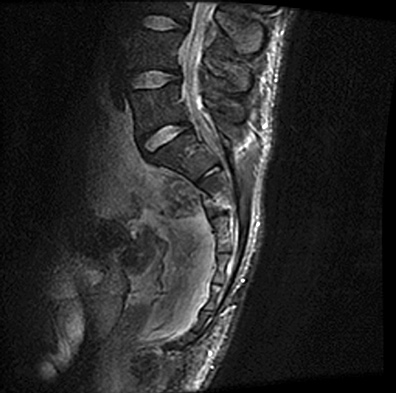

Figures 1 through 3 show sagittal and axial MRIs and a radiograph from a

77-year-old woman with leg pain when standing and walking of 1 year duration. The pain improves when she leans forward. She has been in physical therapy, taken oral analgesics, and had epidural injections with minimal relief. What is the best next step?

The patient has lumbar stenosis of L2-3 and L3-4. She has no spondylolisthesis or instability. For her condition, spinal fusion plays a minimal role. She has no evidence of instability, and her condition can be addressed through laminectomy only. No role exists for microdiskectomy, because her disease results from a combination of ligamentum flavum hypertrophy and facet hypertrophy.